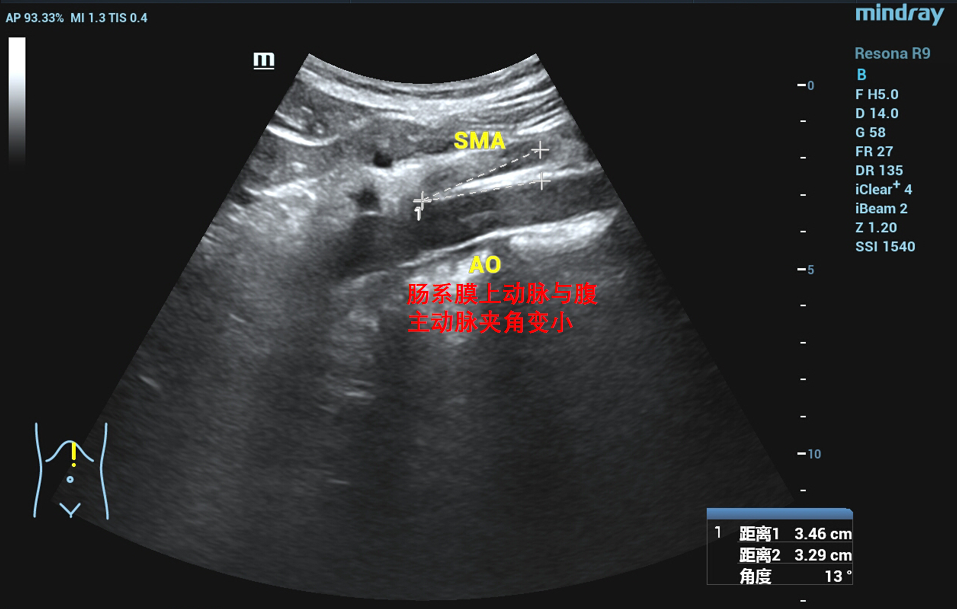

在泌尿外科三病区柯昌兴主任、杨博伟副主任医师、李宇航博士团队的精心准备和密切配合下,顺利为患者完成“腹腔镜(3D)下左肾静脉外支架置入术”。术中,见左肾有3根动脉,其中一根动脉绕行并压迫左肾静脉(术前阅片已确认),左肾静脉入肠系膜上动脉与腹主动脉夹角处,其周围纤维条索较多,此处左肾静脉明显变窄,离断纤维条索后此处左肾静脉明显增宽,充分游离左肾静脉近端至下腔静脉,远端至“其中一根动脉绕行并压迫左肾静脉”处,离断左性腺静脉和肾上腺中央静脉。柯昌兴主任团队成功放置一根6cm长带外支撑环的人工血管固定在患者左肾静脉外面,为受压的左肾静脉支撑起一条“生命通道”,提供持久的支撑力对抗肠系膜上动脉和腹主动脉的压迫。整个手术非常顺利,耗时约3小时,出血约10毫升。术后3天,患者康复出院,且腰痛、血尿等术前临床症状明显缓解,手术效果非常显著。

胡桃夹综合征,也称胡桃夹现象。是指左肾静脉回注下腔静脉过程中,需穿经由腹主动脉和肠系膜上动脉形成的夹角内受到挤压而引起的血尿、蛋白尿和左腰腹疼痛等临床症状。又称为左肾静脉受压综合征。近年来随着诊疗技术的发展。胡桃夹综合征引起的血尿发病率呈逐渐上升趋势,越来越受到临床的关注。

正常情况下,腹主动脉与肠系膜上动脉所形成的夹角为45度到60度,并为脂肪、淋巴、纤维结缔组织等填充,而左肾静脉并不受压。因为某些情况下可使夹角变窄,左肾静脉受压,导致左肾瘀血、肿大,以及左生殖腺静脉瘀血、曲张。